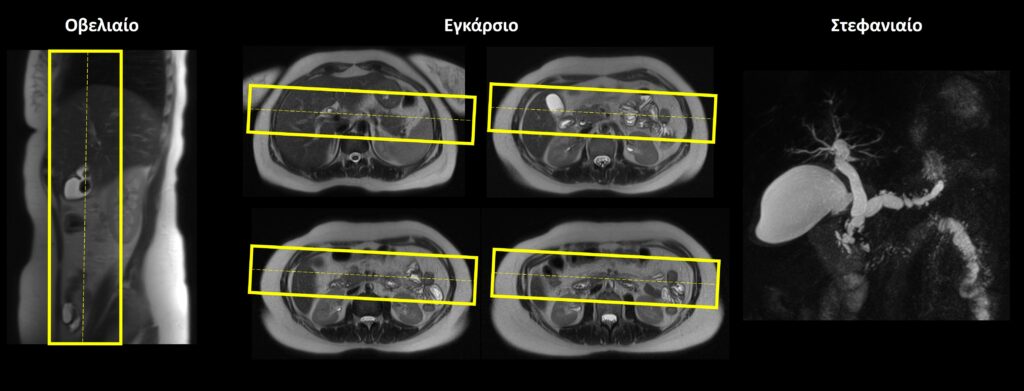

Στεφανιαίο (Coronal) ολόκληρης της κοιλίας: οι στεφανιαίες τομές σχεδιάζονται κατά μήκος των οργάνων της άνω κοιλίας τόσο στο εγκάρσιο όσο και στο οβελιαίο επίπεδο. Δεν απαιτείται ιδιαίτερη κλίση. Οι τομές πρέπει να περιλαμβάνουν ολόκληρη την άνω κοιλία, από το ήπαρ (μπροστά) έως τους νεφρούς (πίσω).

Εγκάρσιο (Axial/Transversal) ολόκληρης της κοιλίας: οι εγκάρσιες τομές σχεδιάζονται κατά μήκος των οργάνων της άνω κοιλίας τόσο στο στεφανιαίο όσο και στο οβελιαίο επίπεδο. Δεν απαιτείται ιδιαίτερη κλίση. Οι τομές πρέπει να περιλαμβάνουν ολόκληρη την άνω κοιλία, από το ήπαρ (πάνω) έως τους νεφρούς (κάτω).